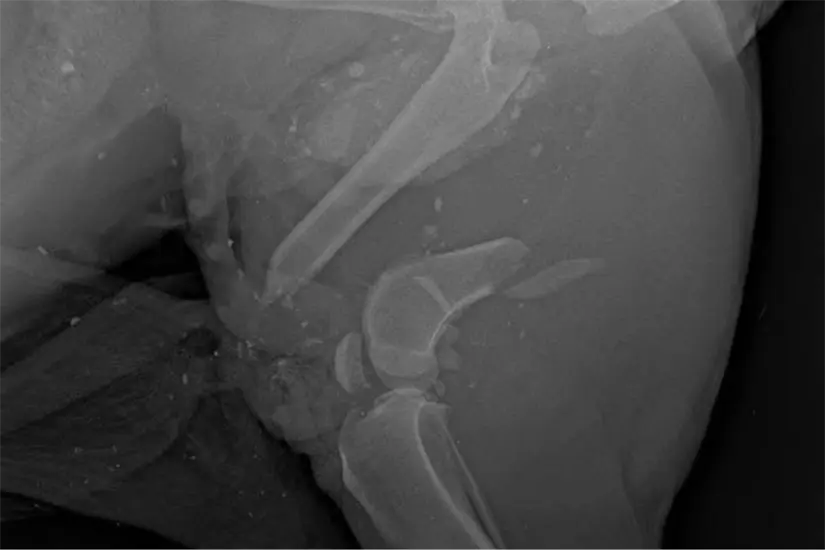

El animal fue localizado con vida tras ser arrollado, con fractura de fémur y posible daño en la vejiga, además de presentar desprendimiento de piel y órganos expuestos, lo que mantiene su condición como grave.

Durante las últimas horas se informó que “Pirata” fue sometido a su primera cirugía con resultados favorables, en la que se le suturó la piel desprendida con más de 30 puntadas. Además, ya se realizaron radiografías para valorar futuras intervenciones quirúrgicas.